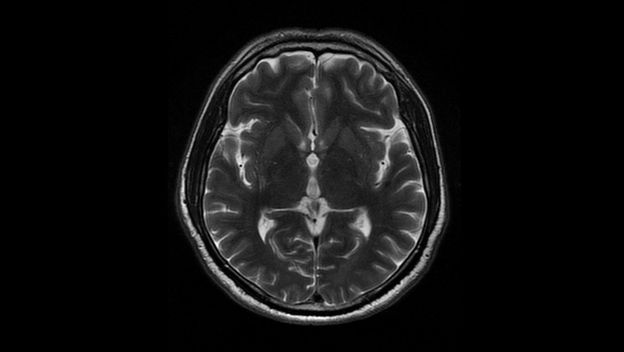

Revolucija u mentalnom zdravlju Brzi lijek protiv depresije? Nova studija otkriva kako takozvani "plin za smijanje" može donijeti olakšanje